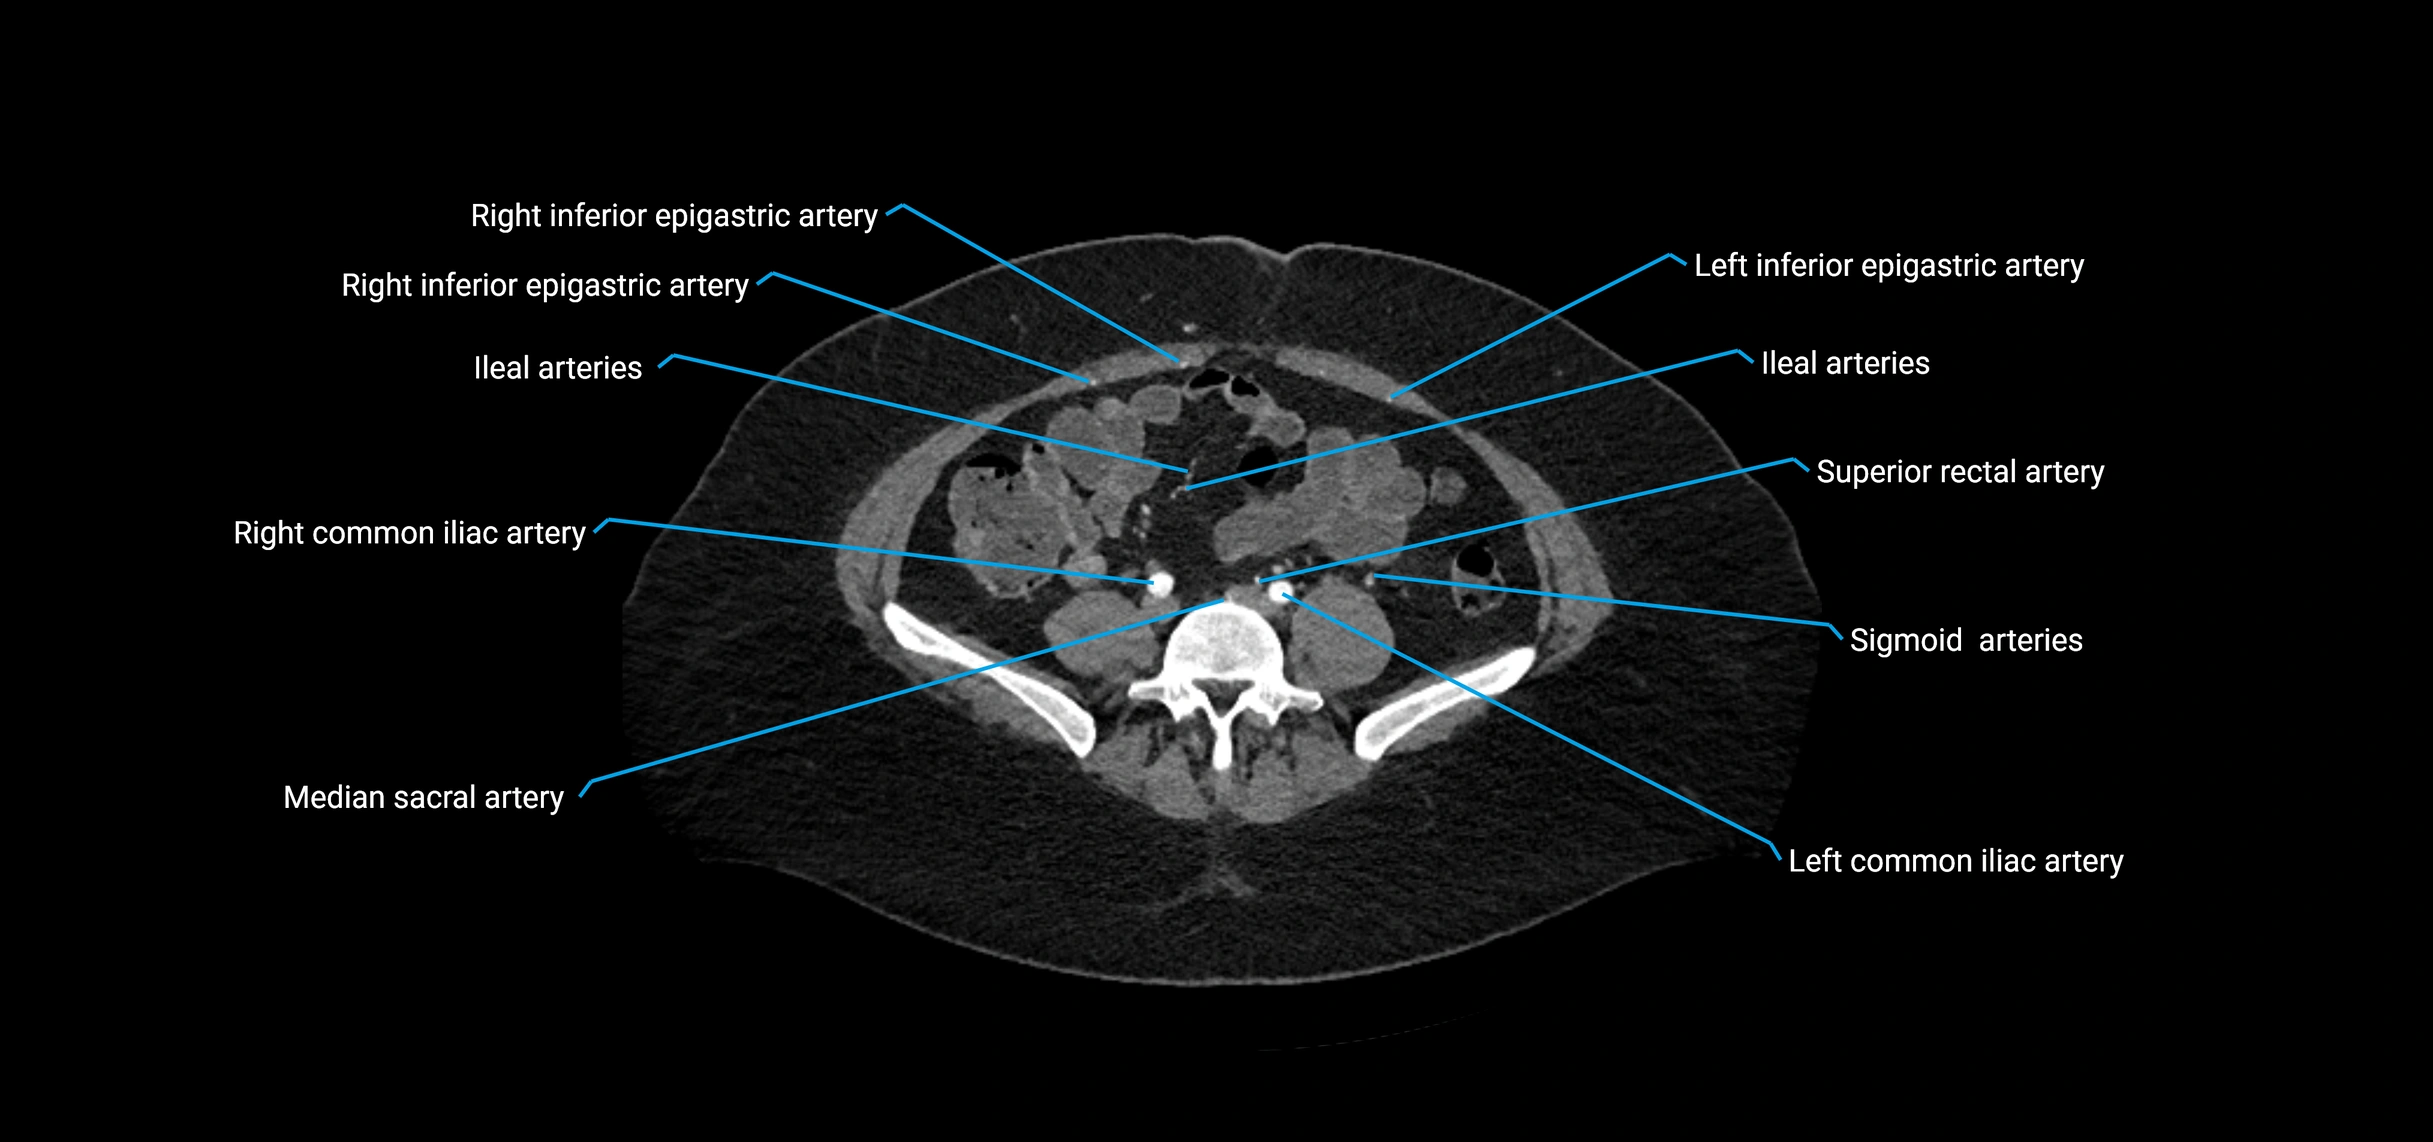

Contrast-enhanced CT (CTA):

• Gold standard for abdominal aortic imaging

• Provides excellent detail of lumen, wall, aneurysm, thrombus, and branch vessels

• Multiplanar and 3D reconstructions help in aneurysm measurement, stent graft planning, and dissection evaluation